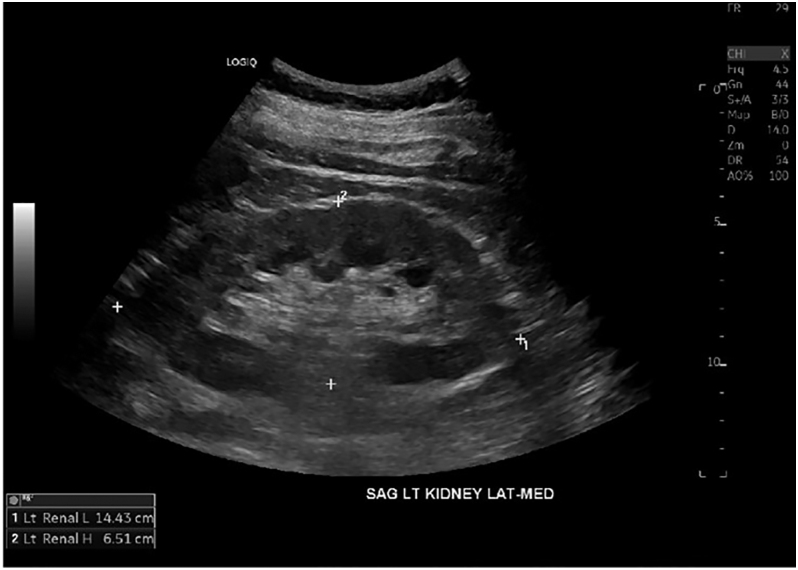

Summary: HDR is a rare autosomal dominant genetic disorder characterized by the triad of hypoparathyroidism, sensorineural deafness and renal anomalies caused by haploinsufficiency loss of function of the GATA-binding protein 3 (GATA3) gene. We present a case of a 56-year-old male diagnosed with hypoparathyroidism, sensorineural deafness, renal hypoplasia and epilepsy. Genetic testing revealed a novel GATA3 heterozygous mutation c.860C>A with a predicted amino acid substitution p.Ala287Asp. This hitherto unreported missense GATA mutation was characterized by a relatively late-onset and milder phenotype of the HDR triad.

Learning points: GATA3 gene mutations located on chromosome 10p cause haploinsufficiency of the GATA3 protein affecting fetal development of the parathyroid glands, inner ear and renal anomalies, resulting in HDR syndrome with an autosomal dominant inheritance pattern.Also known as Barakat syndrome, it has been reported in less than 200 cases with an identified mutation, each having a varied phenotypic presentation without consistent genotypic correlation.We present a patient with HDR syndrome who tested positive for a novel mutation c.860C>A, resulting in a missense substitution of amino acids p.Ala287Asp in the GATA3 gene.Clinicians who identify this rare triad of hypoparathyroidism, sensorineural deafness and renal anomalies should further investigate with genetic testing for GATA3 mutations.